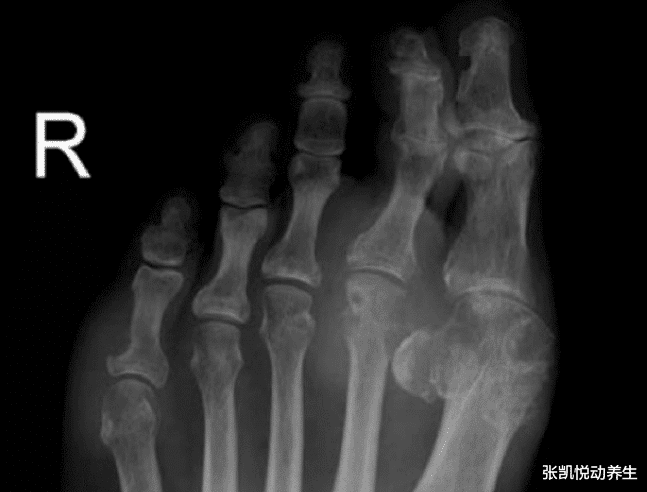

但是某天 , 老王突然四肢抽搐 , 呼吸困难 , 家人立马叫了救护车将老王送进了急救室 , 老王被送去医院前已经3天排尿减少甚至无尿 。 经检查发现 , 病人双手明显变形、手背、手指布满大小不等的痛风结节 , 骨头已被侵蚀 , 形成了所谓的“望远镜手” 。 医生给老王做了血检 , 可怕的是根据检验结果 , 医生发现病人尿酸高达680umol/L , 血肌酐高达700umol/L , 血钾6.8mmol/L , 肾功能明显损害 , 已达到尿毒症情况 , 血钾明显升高 , 随时都可能心脏骤停 。